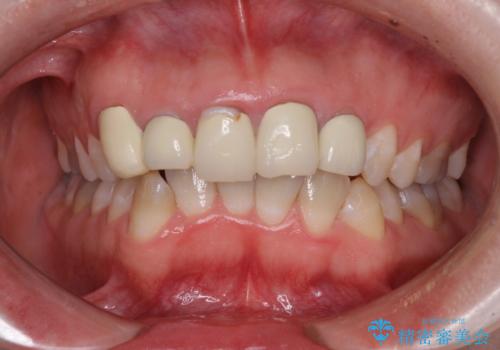

金属の裏打ちを用いたセラミッククラウンであったため歯肉縁に黒ずみが見えてくることは良くありますが、全体的に歯列が不揃いであることが気になったので、それらをオールセラミッククラウンにて改善することとしました。

オールセラミッククラウン装着後、レントゲン写真より精度良く装着されていることは確認できているので、日頃のブラッシングで改善させるよう指導しています。